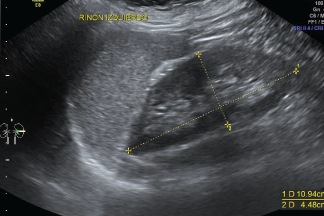

La Ecografía Convencional presenta las imágenes en secciones delgadas y planas del cuerpo.

Esta ecografía es en dos dimensiones o bidimensional, también se conoce como ecografía en blanco y negro.